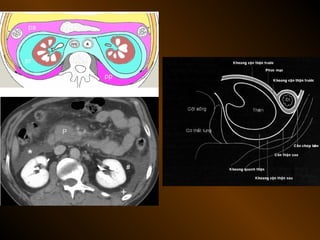

TỤ DỊCH NGOÀI PHÚC MẠC

• Khoang quanh thận

– thận, tuyến thượng thận, niệu quản

• Khoang cận thận trước

– tá tràng, tụy, đại tràng lên, đt xuống

– động mạch gan, lách

• Khoang cận thận sau

– Động mạch chủ bụng, bạch mạch

– Thân đốt sống

– Tá tràng, tụy, đường mật, đại tràng

– Ruột thừa sau manh tràng, đm gan, lách

TỤ DỊCH NGOÀIPHÚC MẠC • Khoang quanh thận – thận, tuyến thượng thận, niệu quản • Khoang cận thận trước – tá tràng, tụy, đại tràng lên, đt xuống – động mạch gan, lách • Khoang cận thận sau – Động mạch chủ bụng, bạch mạch – Thân đốt sống – Tá tràng, tụy, đường mật, đại tràng – Ruột thừa sau manh tràng, đm gan, lách